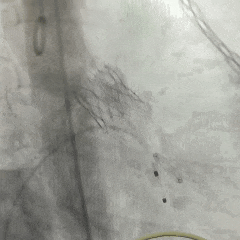

手术过程

左侧冠脉造影

右侧冠脉造影并行PCI

根部造影

可见瓣叶钙化,伴反流

TF21瓣膜0位初始释放

全展开后多角度根部造影:瓣膜深度形态合适,冠脉灌注良好,少量瓣周漏,选择解锁脱钩

脱钩后造影评估:瓣膜深度可,展开良好,少量瓣周漏

外周造影检查,血管无损伤